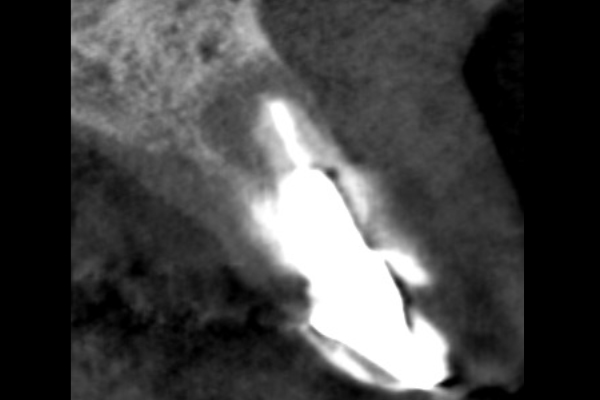

【札幌駅前】精密根管治療

40代女性の前歯部の症例

- 主訴

- 「前歯の歯茎が腫れている」とのことでご来院されました。

数週間前から症状があり、他の医院では「抜歯の可能性がある」と言われ、不安に感じていらっしゃいました。

- 期間

- 治療期間2ヶ月、治療回数3回、レントゲン写真で治癒を確認できるまでの期間6ヶ月

- 治療内容

- 1.古い被せ物の除去と虫歯の徹底除去

まず、古い銀歯を外し、内部に広がっていた虫歯を丁寧に取り除きました。

2.マイクロスコープ下での根管治療

唾液などによる細菌の侵入を防ぐ「ラバーダム」を装着し、マイクロスコープ(歯科用顕微鏡)で根管内を数十倍に拡大しながら治療を進めました。複雑な形状の根管の内部まで、汚染された組織を徹底的に洗浄・消毒します。

3.根管充填(こんかんじゅうてん)

根管内が完全にクリーンになったことを確認し、再感染を防ぐために専用の薬剤で隙間なく密閉しました。

4.土台と被せ物の作製

歯の強度を補うための土台を立て、最終的なセラミックの被せ物を作製し、装着しました。